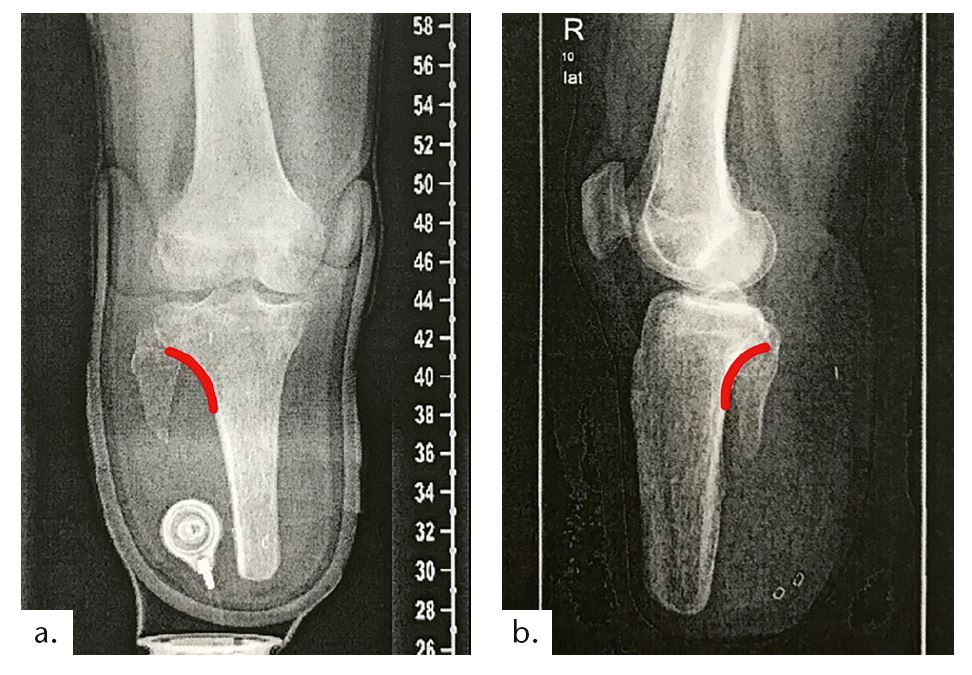

Beim zweiten Fallbeispiel handelt es sich um einen Betroffenen im Alter von 55 Jahren (Mobilitätsgrad 3–4) mit 173 cm Körpergröße bei einem Gewicht von 73 kg. Bei ihm wurde im Alter von 16 Jahren der Unterschenkel aufgrund eines Traumas amputiert. Die Tibialänge beträgt 5,5 cm, die Stumpflänge 6,5 cm mit einer gekürzten Fibula (Abb. 12). Vermutlich aufgrund der Vorversorgungen mit einer PTB-Prothese (PTB = „patellar tendon bearing“) zeigt sich ein Patellahochstand mit daraus resultierender Fehlbelastung und arthrotischer Veränderung. Weil diese Komplikationen als typische Folgen einer PTB-Versorgung anzusehen sind, sollte auf eine solche Versorgung generell verzichtet werden.